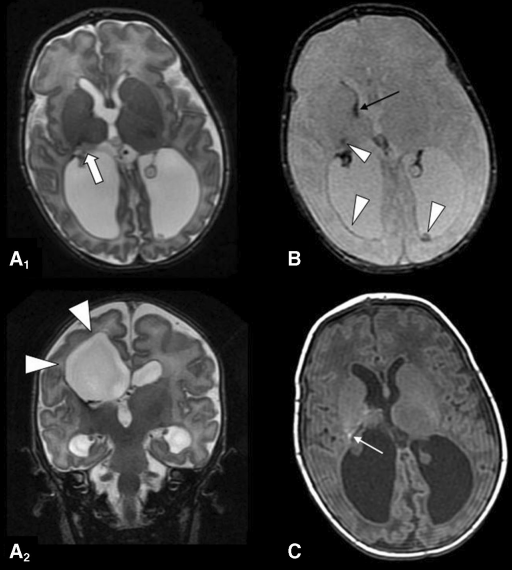

Presurgical TMS evaluation showed a lateralization of motor function on the left motor cortex for both arms,and results were confirmed by MRI studies.Interestingly,after surgery,both epilepsy and motor performances improved and TMS showed enhancement of intracortical inhibition and facilitation activity.

术前经颅磁共振成像(TMS)评估显示双侧手臂左侧运动皮质的运动功能偏侧化,结果经MRI研究证实。然而,术后癫痫和运动能力都得到好转,TMS显示皮质内控制和促进活动增强。